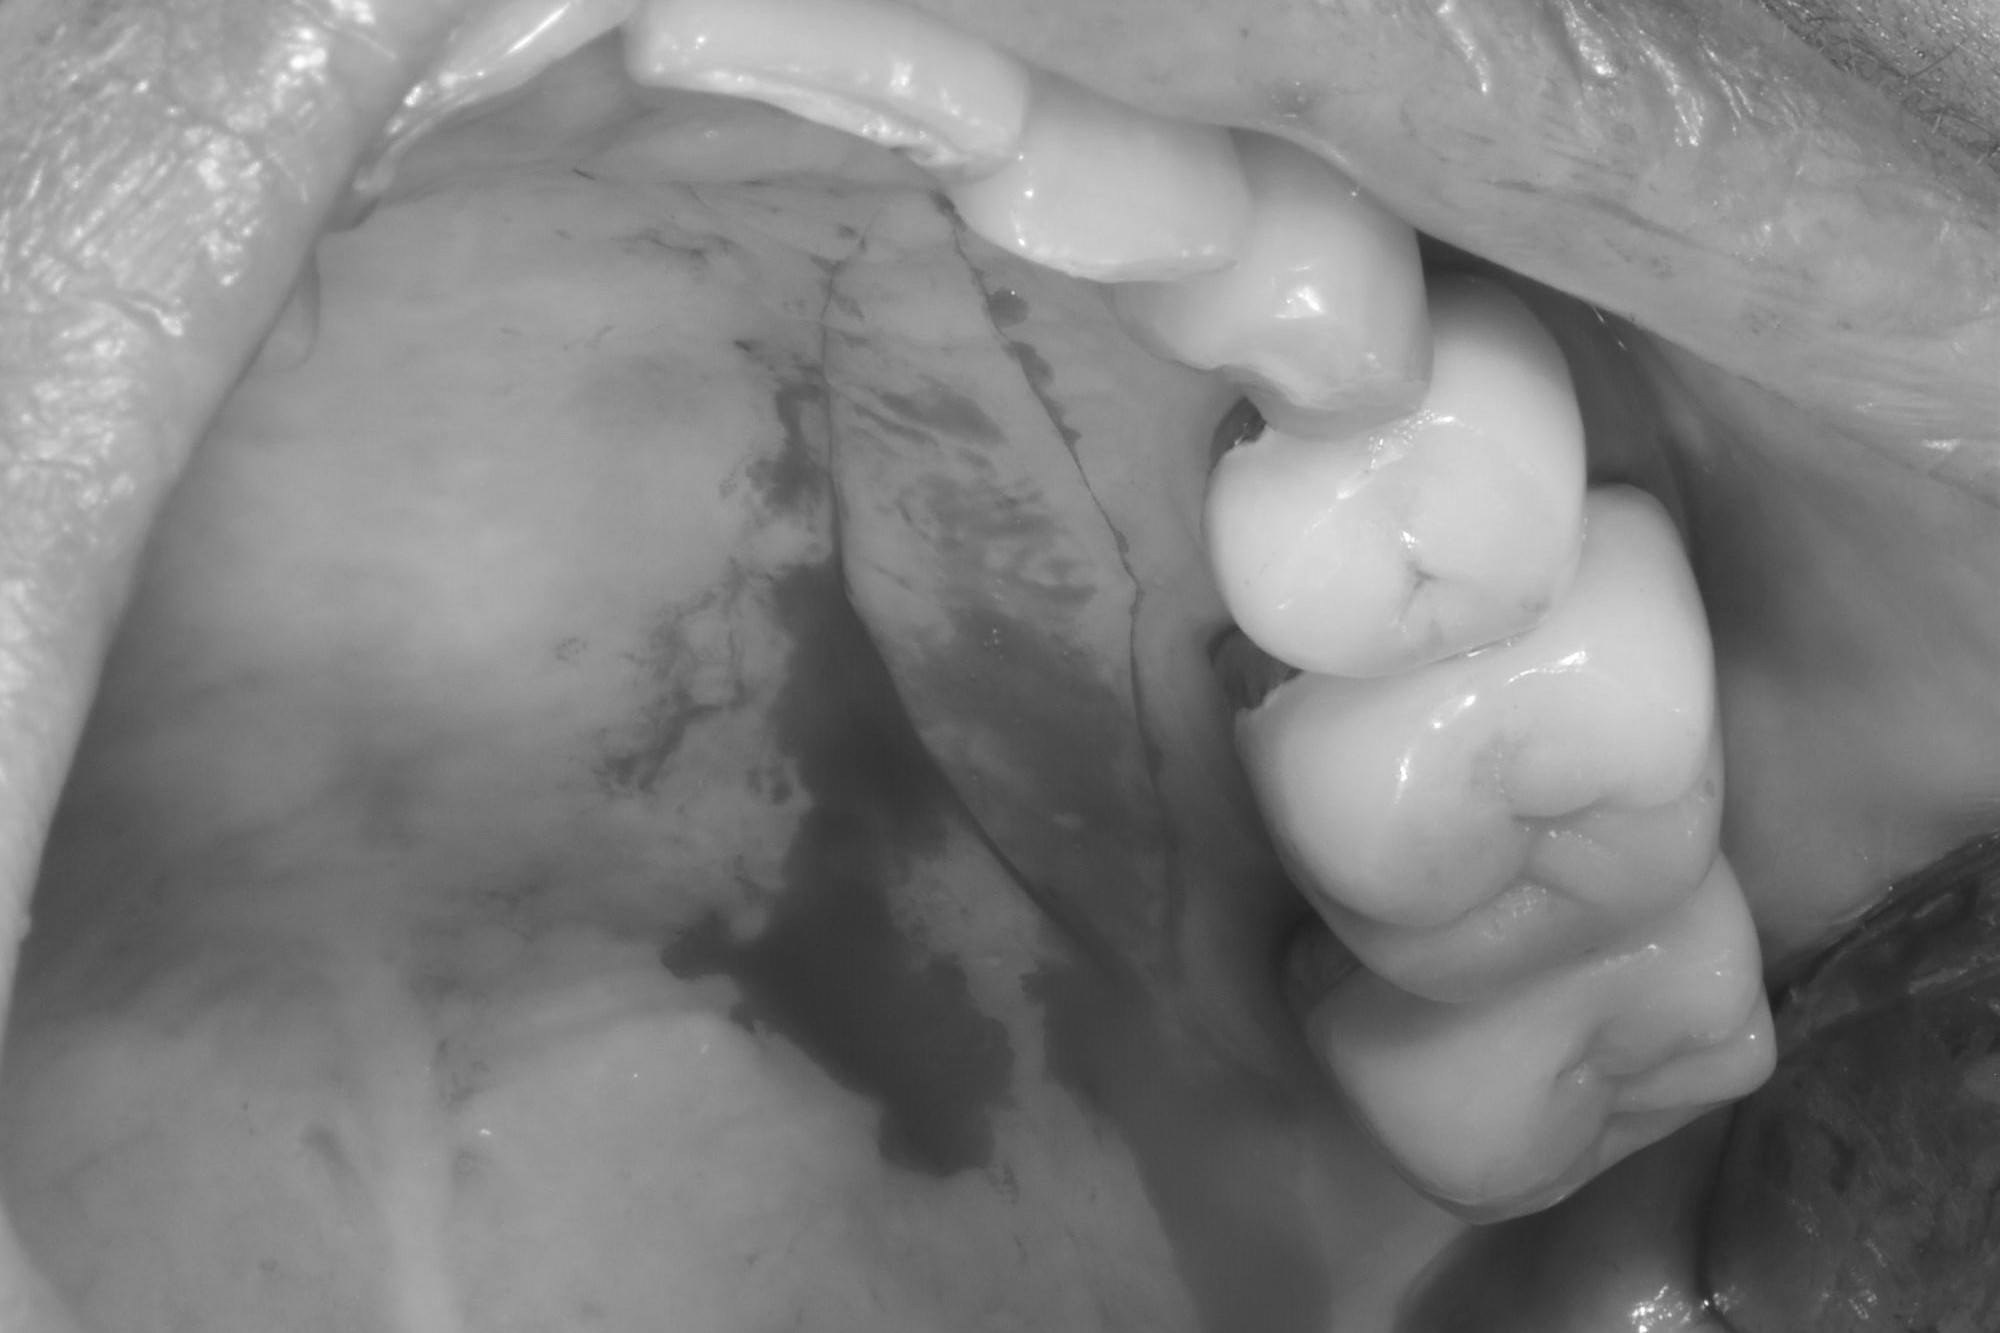

案例三